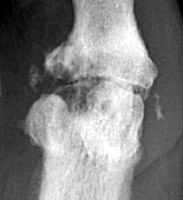

Gout Gout: Large erosion with overhanging edges 1st metatarsal

++